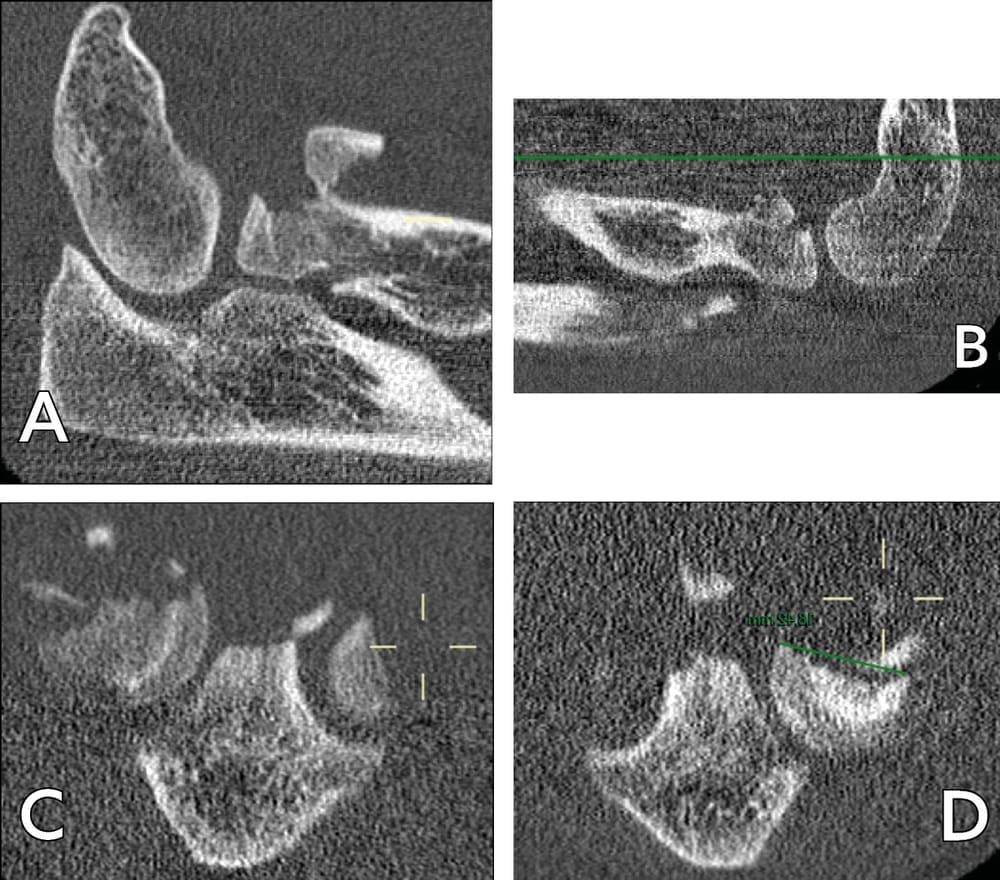

Case study 1: A 49-year-old right-handed male electrician fell from a stepladder, which led to bilateral elbow fracture dislocation (Mason 4). An emergency closed reduction was performed. Subluxation of the left elbow persisted, with damage to the ulnar nerve. After CT investigation (Figure 3), ORIF appeared to be possible, a more viable option since a prosthetic radial head would not be available for at least 5 days.

These similarities were also seen in our second case study: the capitellar diameter measured on CT was found to be identical to that of the radial head (figure 8).